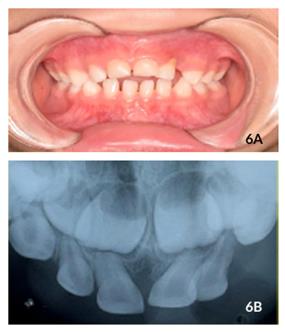

(Figura 4C). Ao acompanhamento de 8 meses, constatou-se que o dente #61 reerupcionou satisfatoriamente apesar de estar ligeiramente acima da linha de oclusão e o paciente apresentar mordida aberta anterior. Novamente, foram observados ausência de inflamação gengival, fístula ou sintomatologia dolorosa (Figura 5A). Além disso, em relação ao dente #62, observou se acúmulo de biofilme dental, vermelhidão e inchaço na gengiva inserida adjacente, com recessão gengival na região cervical devido à interferência oclusal, mobilidade grau I e reabsorção radicular externa (Figura 5B). Ao exame radiográfico, não há sinais de lesões periapicais e lesões periodontais no dente #61. O paciente estava

assintomático e não houve necessidade de intervenção. Ao acompanhamento de 12 meses após o trauma, o paciente retornou com as mesmas características do último atendimento (Figuras 6A e 6B).